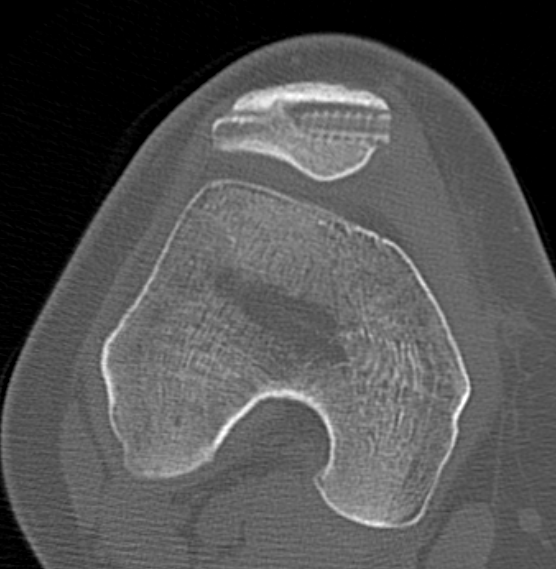

1. Isolated Patella tilt

Indications

- clinical and xray patella tilt

- no instability / malalignment

- excessive lateral pressure syndrome